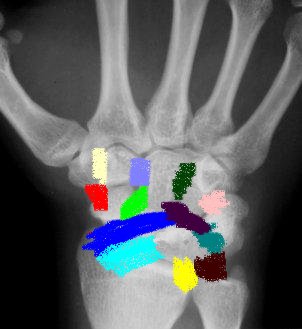

Radiographs

Radiographs reveal  key features of rotatory subluxation of the scaphoid.

Ap view

"Terry Thomas"sign gap between scaphoid and lunate normal 1-2 mm (abnormal 3mm)

Progressive flexion and foreshortening of the scaphoid leads to the scaphoid ring sign, seeing scaphoid end on.

Lateral view

Increased scapholunate angle normal 30-60º

Increased flexion of scaphoid and extension of lunate may progress to DISI (increase capitolunate angle >20º strongly suggestive of carpal instability